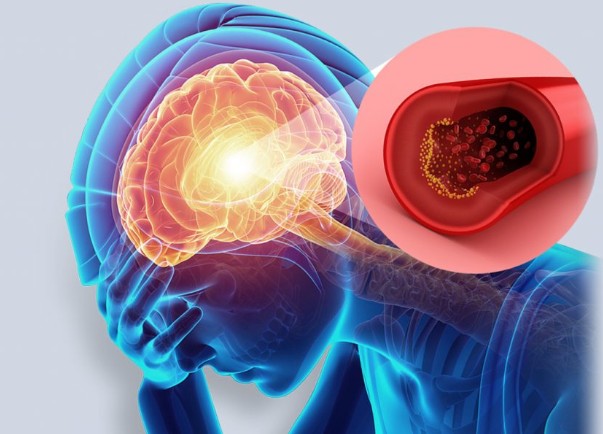

뇌졸중 전조증상 10. 일시적인 증상 후 정상으로 돌아오는 TIA (일과성 허혈 발작)

이전의 증상들 중 일부가 수 분~수십 분 내 회복되는 경우가 있습니다.

이러한 증상을 **TIA(일과성 허혈 발작)**이라고 하며,

뇌졸중의 ‘전조경고’이자 ‘예고편’과 같은 매우 중요한 징후입니다.

TIA 발생 후 90일 이내에 약 1/3은 뇌졸중으로 진행될 수 있으므로 즉시 병원 검진이 필요합니다.뇌졸중 전조증상 주의사항